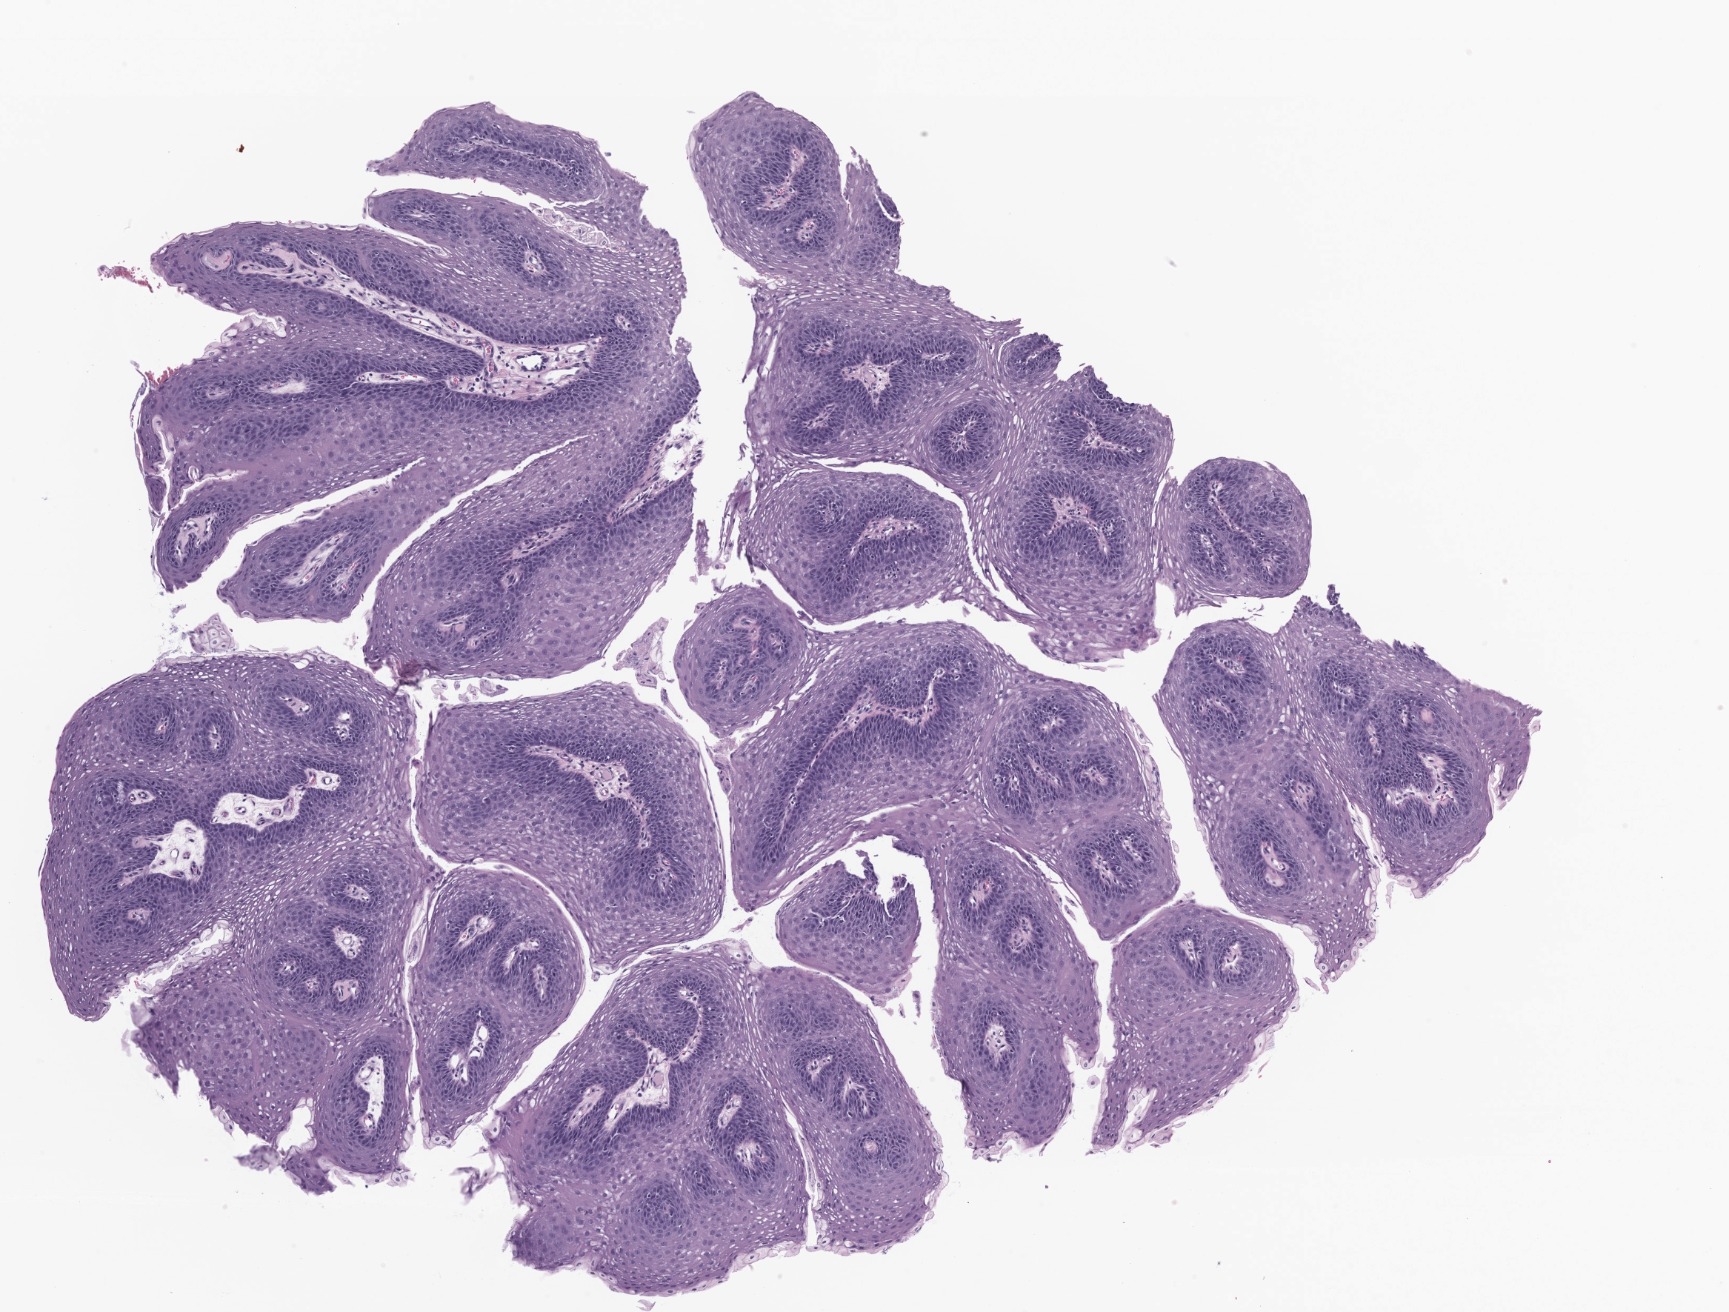

Microscopic (histologic) description

- Finger-like projections or multiple fronds with a central fibrovascular core, covered by benign hyperplastic stratified squamous epithelium

- Basal and parabasal hyperplasia

- Increased mitotic figures in the basal and parabasal layers

- Koilocytic changes in upper layer: may be pronounced or subtle

- Surface keratinization: absent to minimal

Microscopic (histologic) images